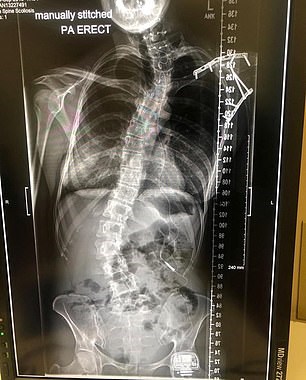

Ωστόσο, σε ένα φρικιαστικό ατύχημα έπεσε πάνω στην κάμερα και τραυματίστηκε σοβαρά, τόσο στο πρόσωπο όσο και στο αριστερό της χέρι, το οποίο έπρεπε να ακρωτηριαστεί. Επίσης. υπέστη τραύμα στον εγκέφαλο και παράλληλα συνεθλίβη ζωτική αρτηρία στον λαιμό. Στη μακρά λίστα τραυμάτων προστίθενται η μετατόπιση σπονδυλικής στήλης, η μόνιμη εξάρθρωση ώμου, σπασμένος αντίχειρας, διάτρητα πνευμόνια και σπασμένα πλευρά.